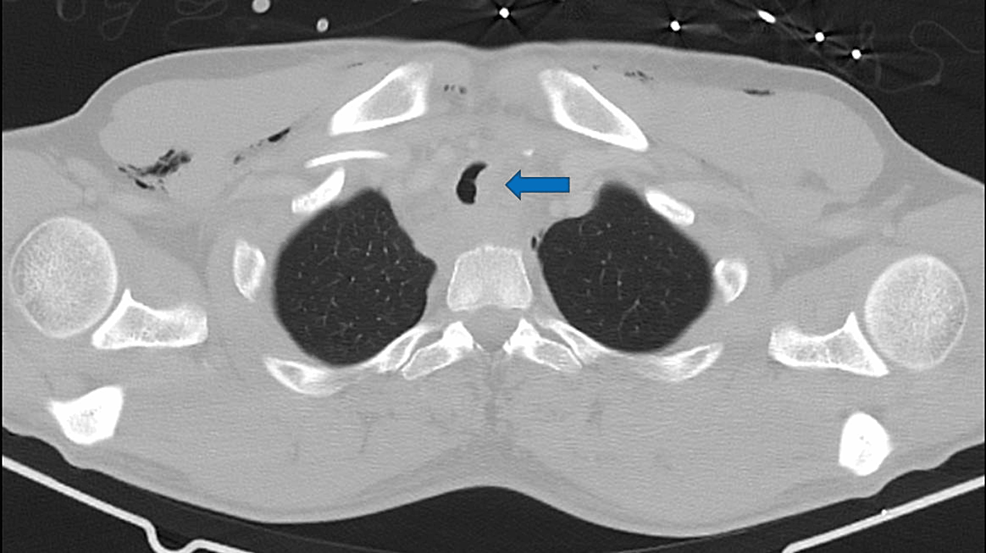

Thoracic CT showing posterior tracheal rupture (Arrow). Download Tracheal Rupture The major causes of tracheal injury include iatrogenic, blunt trauma, penetrating trauma, inhalation and aspiration of liquids or objects. Tracheobronchial tears are uncommon injuries or lacerations or puncture occurring anywhere in the tracheobronchial tree resulting from penetrating or blunt trauma to the neck or. Common etiologies include blunt or penetrating. A tracheal or bronchial rupture is a tear or break. Tracheal Rupture.